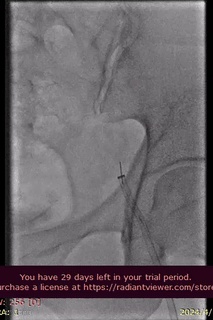

手术过程